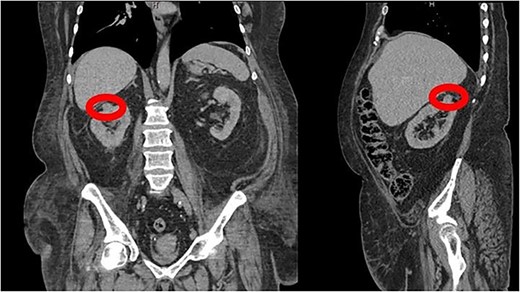

A 66-year-old morbidly obese female with relevant past medical history of type 2 diabetes mellitus, hypertension, and end stage renal disease on peritoneal dialysis (PD) was found to have an incidental enhancing right renal mass concerning for neoplasm on computerized tomography (CT) urogram workup for bacterial peritonitis secondary to streptococcus agalactiae bacteremia (Figs 1 and 2). After appropriate antibiotic treatment and discharge, the patient followed up in clinic where review of the incidental exophytic 16 mm renal mass confirmed suspicions for renal cell carcinoma. The patient still produced urine and was on the transplant list, but wished to proceed with RAPN of the suspicious lesion. A decision was made to use the patient’s PD catheter given her preoperative score of >3 on the Hostile Abdomen Index [5]. In addition to history of bacterial peritonitis, the patient had a notable past surgical history of open cholecystectomy, umbilical hernia repair, and laparoscopic peritoneal dialysis catheter placement in the past 3 months. She was also awaiting a transplant donor, and wished to remain on the list. In the operative theater, her double-cuffed Tenckhoff PD catheter was capped and prepped into the sterile field. Insufflation tubing was connected to the PD catheter and pneumoperitoneum was achieved with normal opening pressure. Laparoscopic trocars were sequentially placed and RAPN was completed without complication. The patient’s post-operative course was unremarkable. Upon physical examination at her 1 month follow-up, her incision sites remained clean, dry, and intact with no complaints of pain. She denied dysuria and gross hematuria. She was cleared to restart peritoneal dialysis at that time. Subsequent pathologic examination of the renal mass confirmed Type 2 Renal Cell Carcinoma with pathologic stage classification T1a, N0 and no signs of regional lymph node metastasis. The patient was instructed to follow-up in 6 months but was ultimately lost to follow-up on our urologic service.

CT Urogram demonstrating a 1.6 cm enhancing right renal mass suspicious for renal cell carcinoma.

CT Urogram demonstrating right renal mass suspicious for neoplasm.